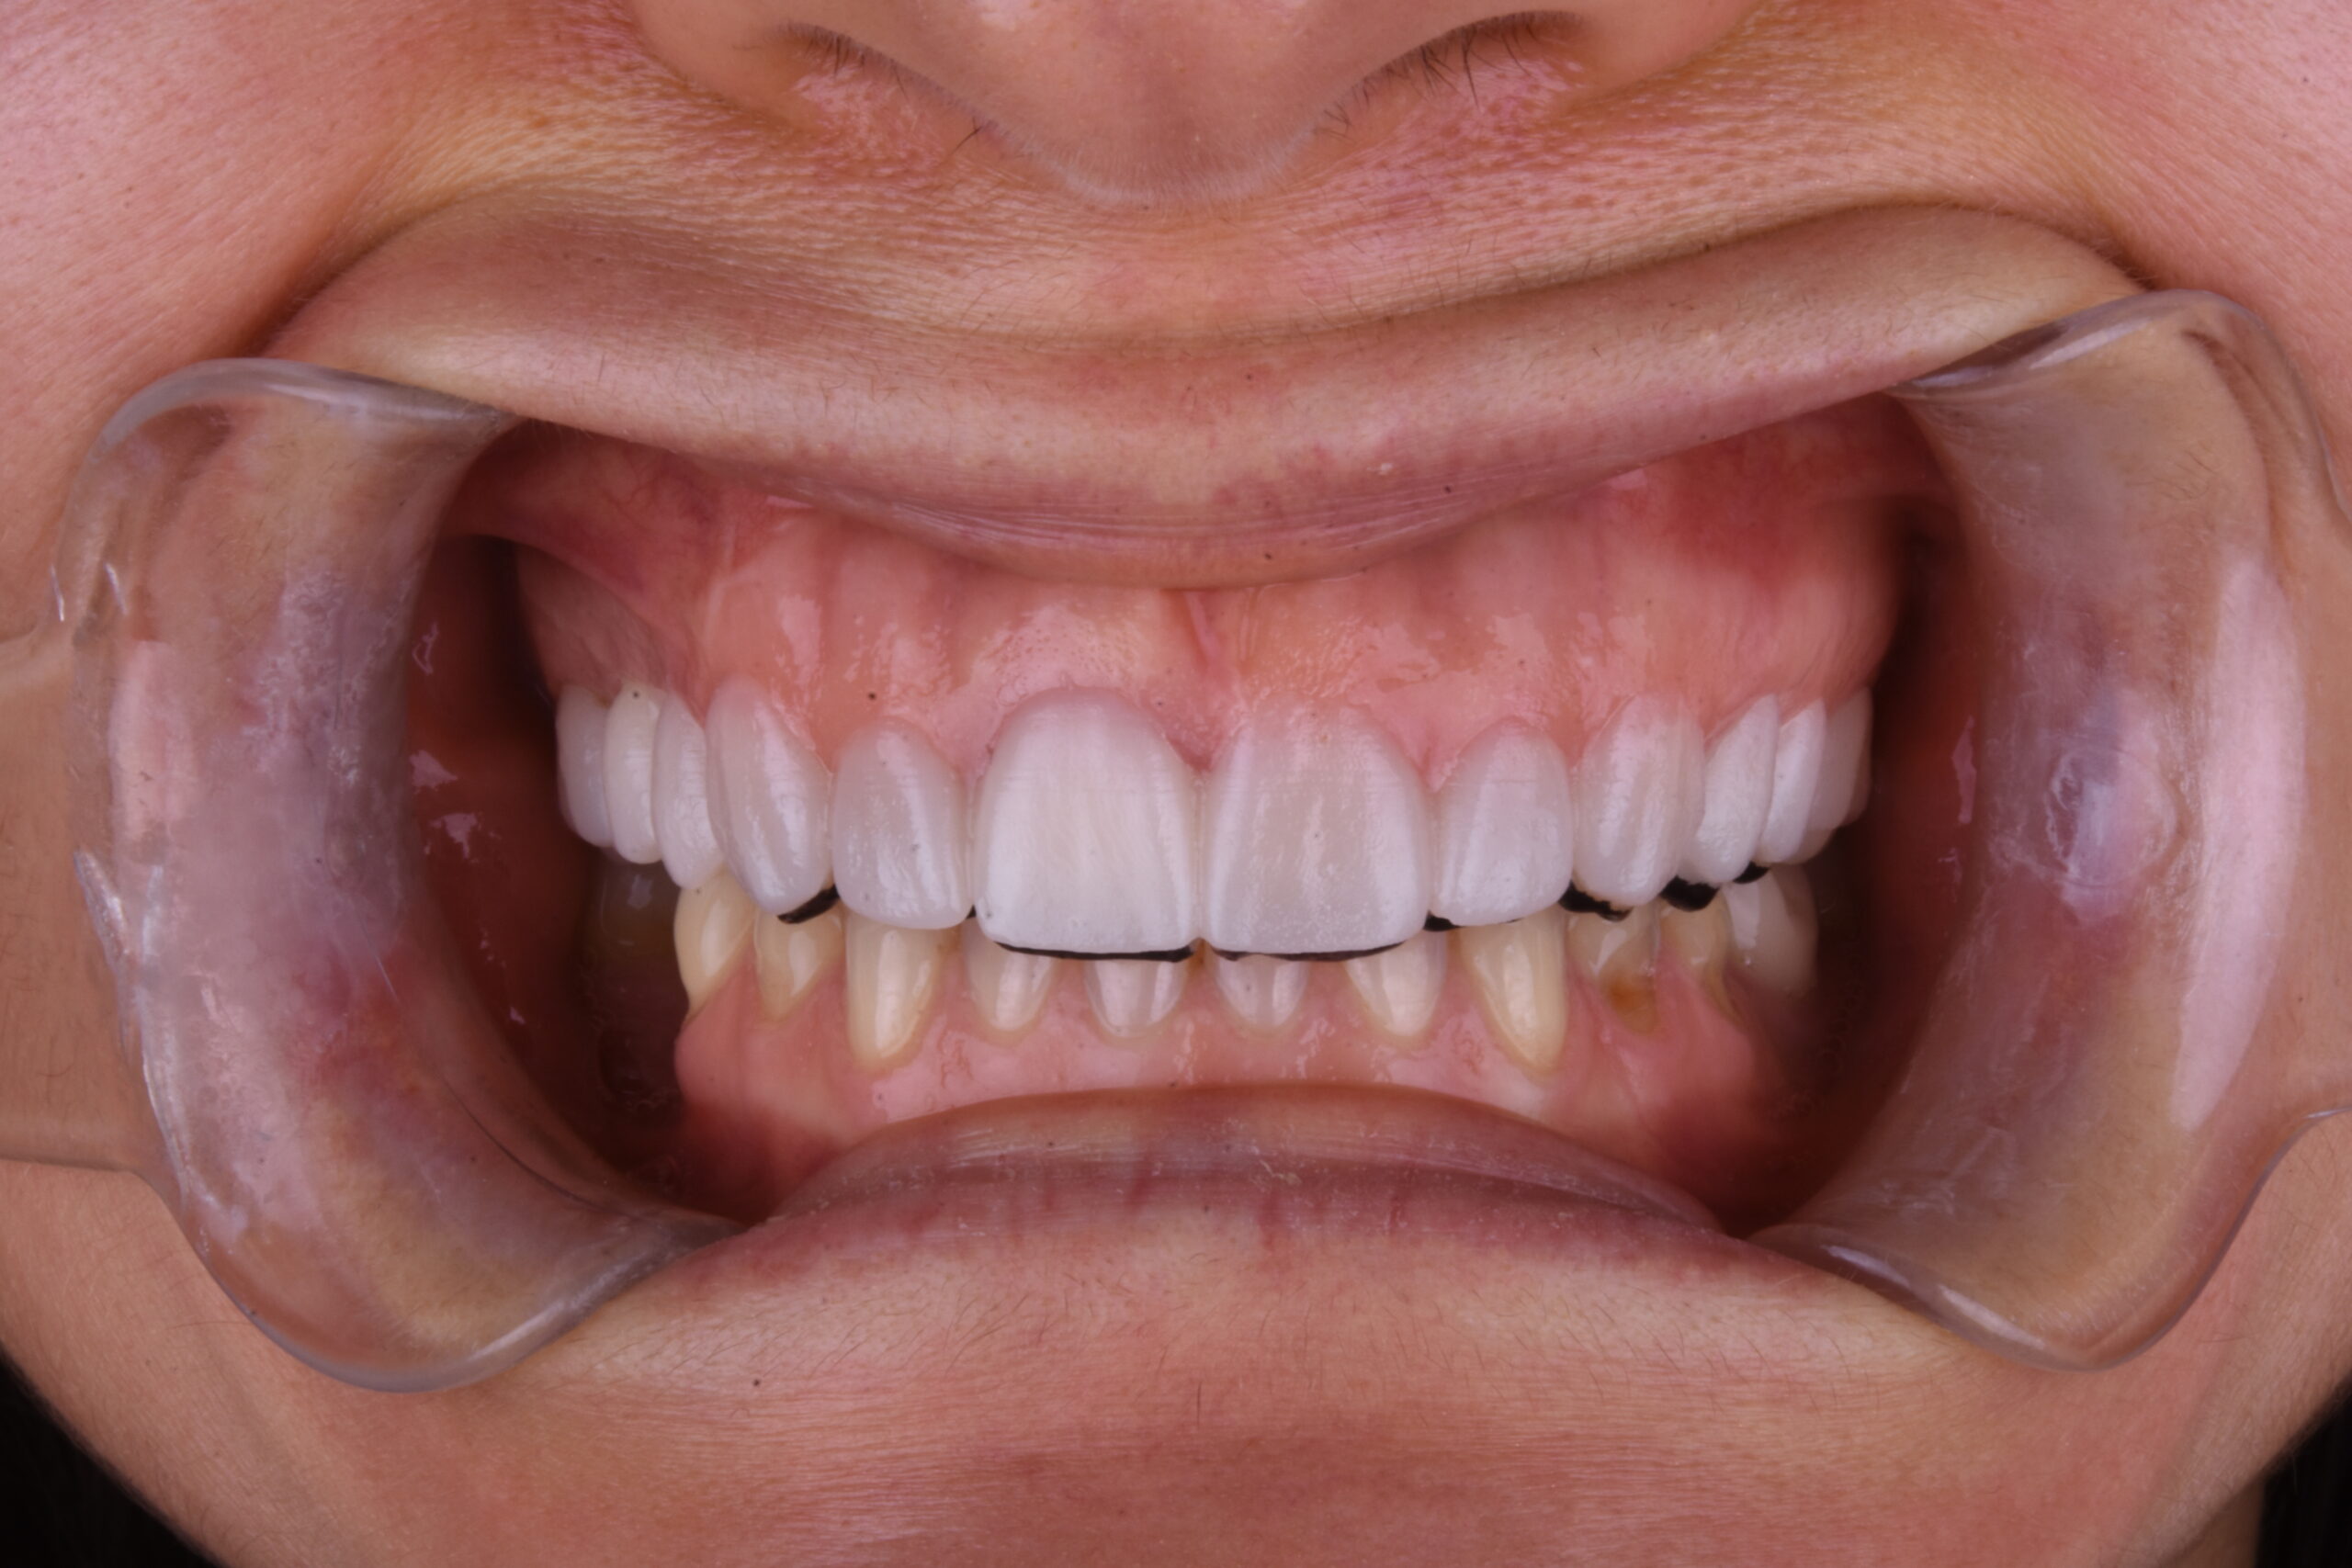

Resultados Resultados

Antes del tratamiento Sorriso depois do tratamento

Devolverle el alma y vestiral con una bella sonrisa como decia su madre consiguiendo esos dientes blanquitos que tanto deseaba, respetando una buena oclusion y dinamica mandibular